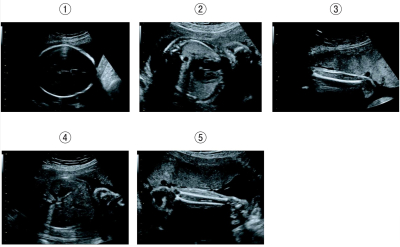

胎児の超音波断層像を別に示す。胎児推定体重を測定する際に用いるのはどれか。3つ選べ。

a. ①

b. ②

c. ③

d. ④

e. ⑤

①は児頭大横径 推定可能

③は大腿骨長 推定可能

④は躯幹周囲長 推定可能